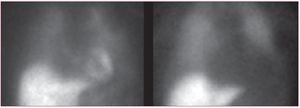

La gammagrafía cardiaca obtenida con 123I-metayodobenzil-guanidina para la valoración de la inervación simpática (fig. 7) es otra herramienta útil para la estratificación del riesgo en los pacientes con insuficiencia cardiaca130. En el estudio prospectivo ADMIRE-HF131, que incluyó a 961 pacientes en clase funcional II/III y fracción de eyección ventricular izquierda ≤ 35%, se objetivó peor pronóstico, en cuanto a progresión de la insuficiencia cardiaca, arritmias graves y muerte en un seguimiento de 2 años, en los pacientes con una relación de captación corazón/mediastino < 1,6 a las 4 h de la inyección del radiofármaco. Las complicaciones arrítmicas graves (taquicardia ventricular autolimitada, parada cardiaca resucitada, descarga apropiada del desfibrilador) o la muerte súbita fueron excepcionales en los pacientes con una relación de captación corazón/mediastino > 1,6. En esta serie, un 21% de los pacientes tenían una relación corazón/mediastino ≥ 1,6, por lo que a raíz de estos resultados podría plantearse una revisión de las indicaciones de implantación del desfibrilador si esta exploración se introduce para la estratificación de riesgo de enfermos en las unidades de insuficiencia cardiaca.

Figura 7. Gammagrafías planares de inervación cardiaca obtenidas con I-metayodobenzil-guanidina. A la izquierda, un ejemplo de inervación normal con una relación de captación corazón/mediastino > 2. A la derecha, la imagen obtenida en un paciente con miocardiopatía isquémica e insuficiencia cardiaca de grado III, en la que prácticamente no es visible la captación cardiaca y la relación corazón/mediastino es < 1 (imagen cedida por el Dr. Santiago Aguadé-Bruix, Servicio de Medicina Nuclear del Hospital Universitari Vall d'Hebron, Barcelona).